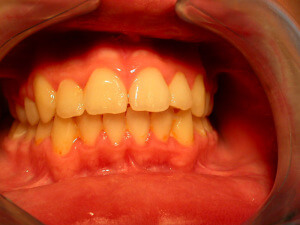

Gingivitis

Gingivitis is caused to the bacterial dental plaque. The main problems related to gingivitis are bleeding from the gums (during tooth brushing), halitosis and swelling of the gums.

Except for the bad oral hygiene, gingivitis is related to hormonal changes during puberty or pregnancy, or the presence of orthodontic mechanisms in the mouth that make difficult to maintain good oral hygiene.

Ways of Gingivitis Prevention

The best way to treat gingivitis is to prevent it.